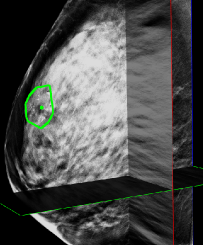

(b) A DBT volume

Figure 1: (a) Left: An example of a malignant mammography screening image from GE Senographe mammography system showing the difficulty of finding MC groups. Right top: The local MC group region. The region is small and MCs are barely visible even with adjusted window level to enhance contrast. Right bottom: The ground truth of individual MCs (the bounding boxes), and the malignant group (the convex hull contour). (b) An example of GE SenoClaire DBT volume with manually labeled group contour on one slice (the green contour). The inter-slice boundaries of the group are labeled as green points.

A large number of literature has been reported on creating CAD system for MC groups in 2D mammography (as in Figure 1(a)). However, publications on CAD for recently emerged DBT (as in Figure 1(b)) are very limited. This is due to the difficulty of collecting enough cancer cases to train a DBT CAD from scratch. Instead, most researchers built systems on small DBT datasets with limited training [1, 2] or applied a mammography CAD directly on slices or projections of DBT volumes [3, 4, 5].